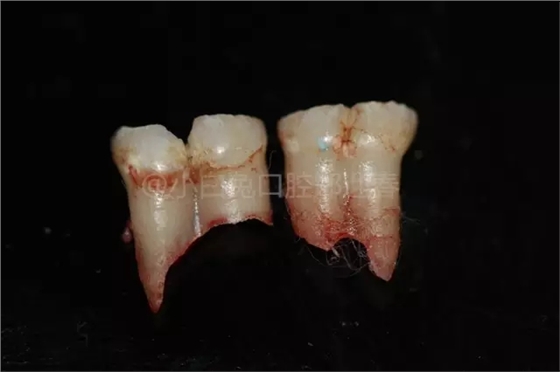

拔出后的離體牙